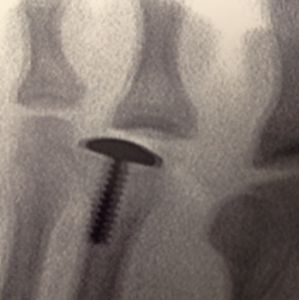

Titanium Cap

As for treatment, I have been successful with resecting the infarction and replacing it with a titanium cap.

Sloan Gordon, DPM, Houston, TX, sgordondoc@sbcglobal.net